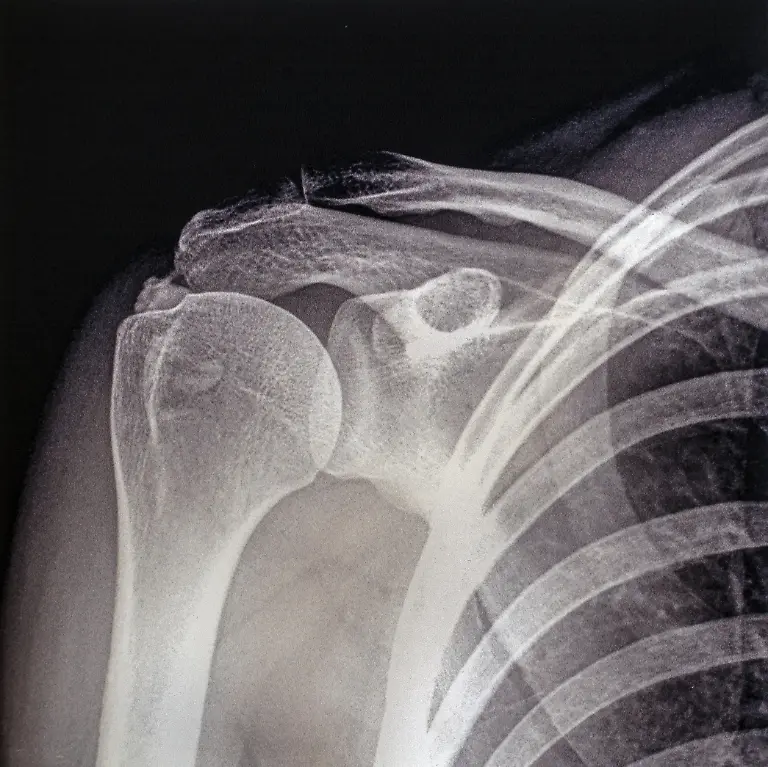

Er war ein Revolutionär der Medizintechnik: Der Physiker Wilhelm Conrad Röntgen entdeckte 1895 zufällig die X-Strahlen, was nicht nur für die Diagnostik in der Medizin ein Meilenstein war. Später wurden die Strahlen und das Verfahren nach ihm benannt. Röntgen starb vor 100 Jahren in München.